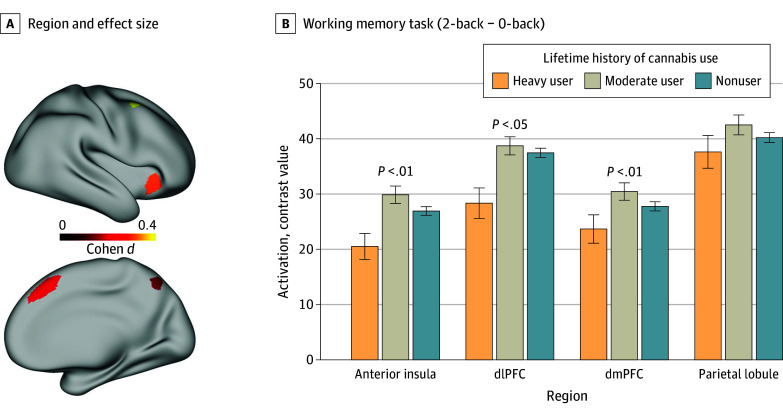

For statistically significant results of brain activation, we conducted post hoc analysis to determine which regions were associated with the result. This involved running separate linear mixed-effects models as specified earlier for each brain region (eg, for the working memory task, the 4 regions included the anterior insula [AVI], the superior parietal lobule [7Pm], the medial PFC [8BM], and the dorsolateral PFC [i6-8]).

For the working memory task, the models for the anterior insula, medial PFC, and dorsolateral PFC showed associations with lifetime history of cannabis use (all t < −2.0; all P < .02), as shown in Figure 4 (full models are displayed in eTables 13-16 in Supplement 1). However, the model for the superior parietal lobule (t = −1.6; P = .10) did not.

In this study, lower brain activation during the working memory task in heavy cannabis users was most pronounced in the dorsolateral PFC, dorsomedial PFC, and anterior insula. These are regions that have a relatively high density of CB1 receptors and where receptor availability was found to be reduced in association with daily cannabis exposure.47 Similarly, rodent studies showed that THC exposure reduced the density and sensitivity of CB1 receptors in these brain regions,48 providing evidence that heavy cannabis use can cause neural adaption. Because THC can reduce CB1 density, this could provide a mechanism to explain findings that cannabis use is associated with lower cortical thickness in the dorsomedial PFC and dorsolateral PFC.16 The impact of these putative effects was observed on the working memory task in the current study. A previous study that examined the HCP data also showed that recent cannabis use was associated with lower activation during the working memory task in the anterior insula and middle frontal gyrus, and that their decreased activation mediated the association between cannabis use and poorer performance on an episodic memory task.49,50 Our results are consistent with these findings, although they suggest that heavy lifetime cannabis use among participants was associated with lower activation to a working memory task even after removing individuals with a positive urine screen at the time of testing to control for recent use. This finding also accords with evidence that heavy cannabis use alters brain activation in the absence of recent use51 and that acute THC administration reduces brain activation in brain regions involved in working memory.52